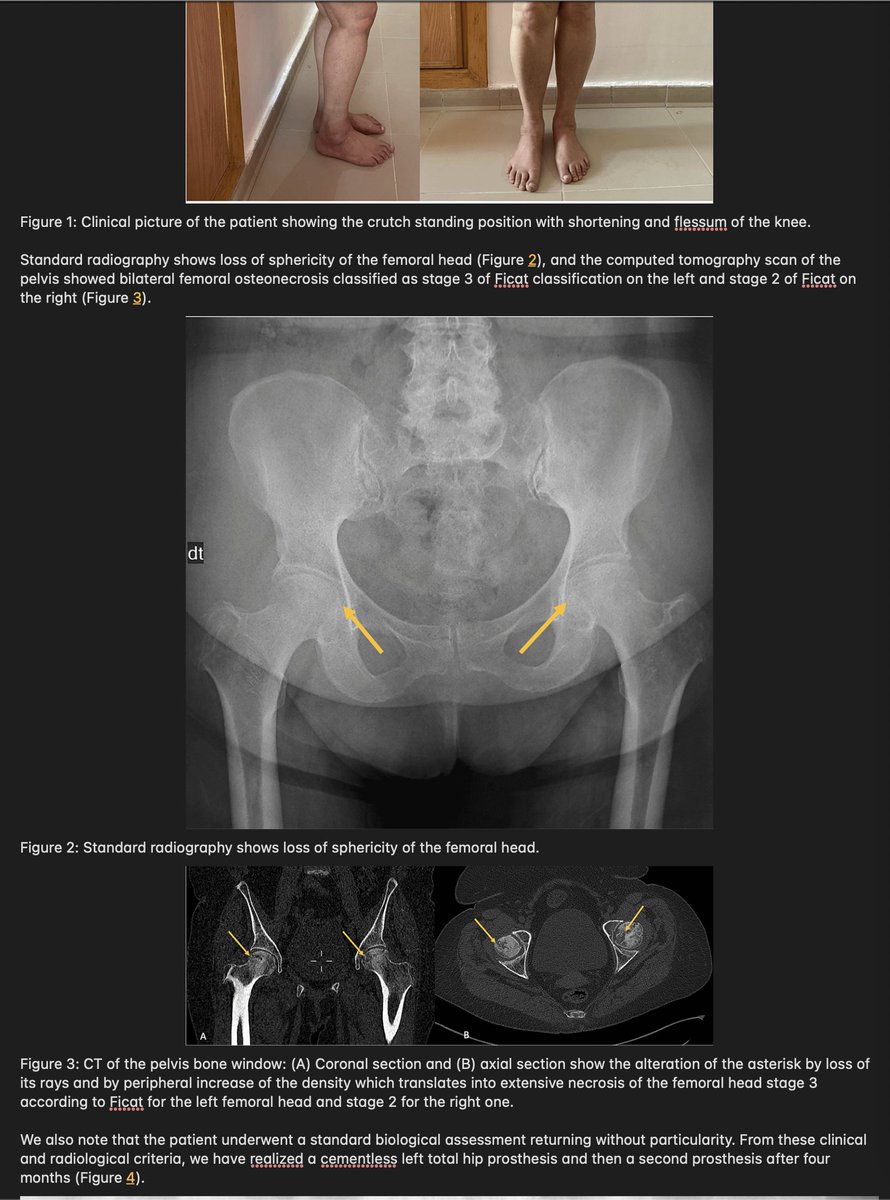

Post-COVID-19 Femoral Head Osteonecrosis Exhibits Mast Cell Clusters, Fibrosis, and Vascular Thrombosis: Key Pathological Mechanisms in Long COVID-19 Bone Degeneration 🔥For many a new #LC presentation needing THR(Total Hip Replacement)😲 ➡️'Оsteonecrosis of the femoral head…

🔥For many a new #LC presentation needing THR(Total Hip Replacement)😲

➡️'Оsteonecrosis of the femoral head…